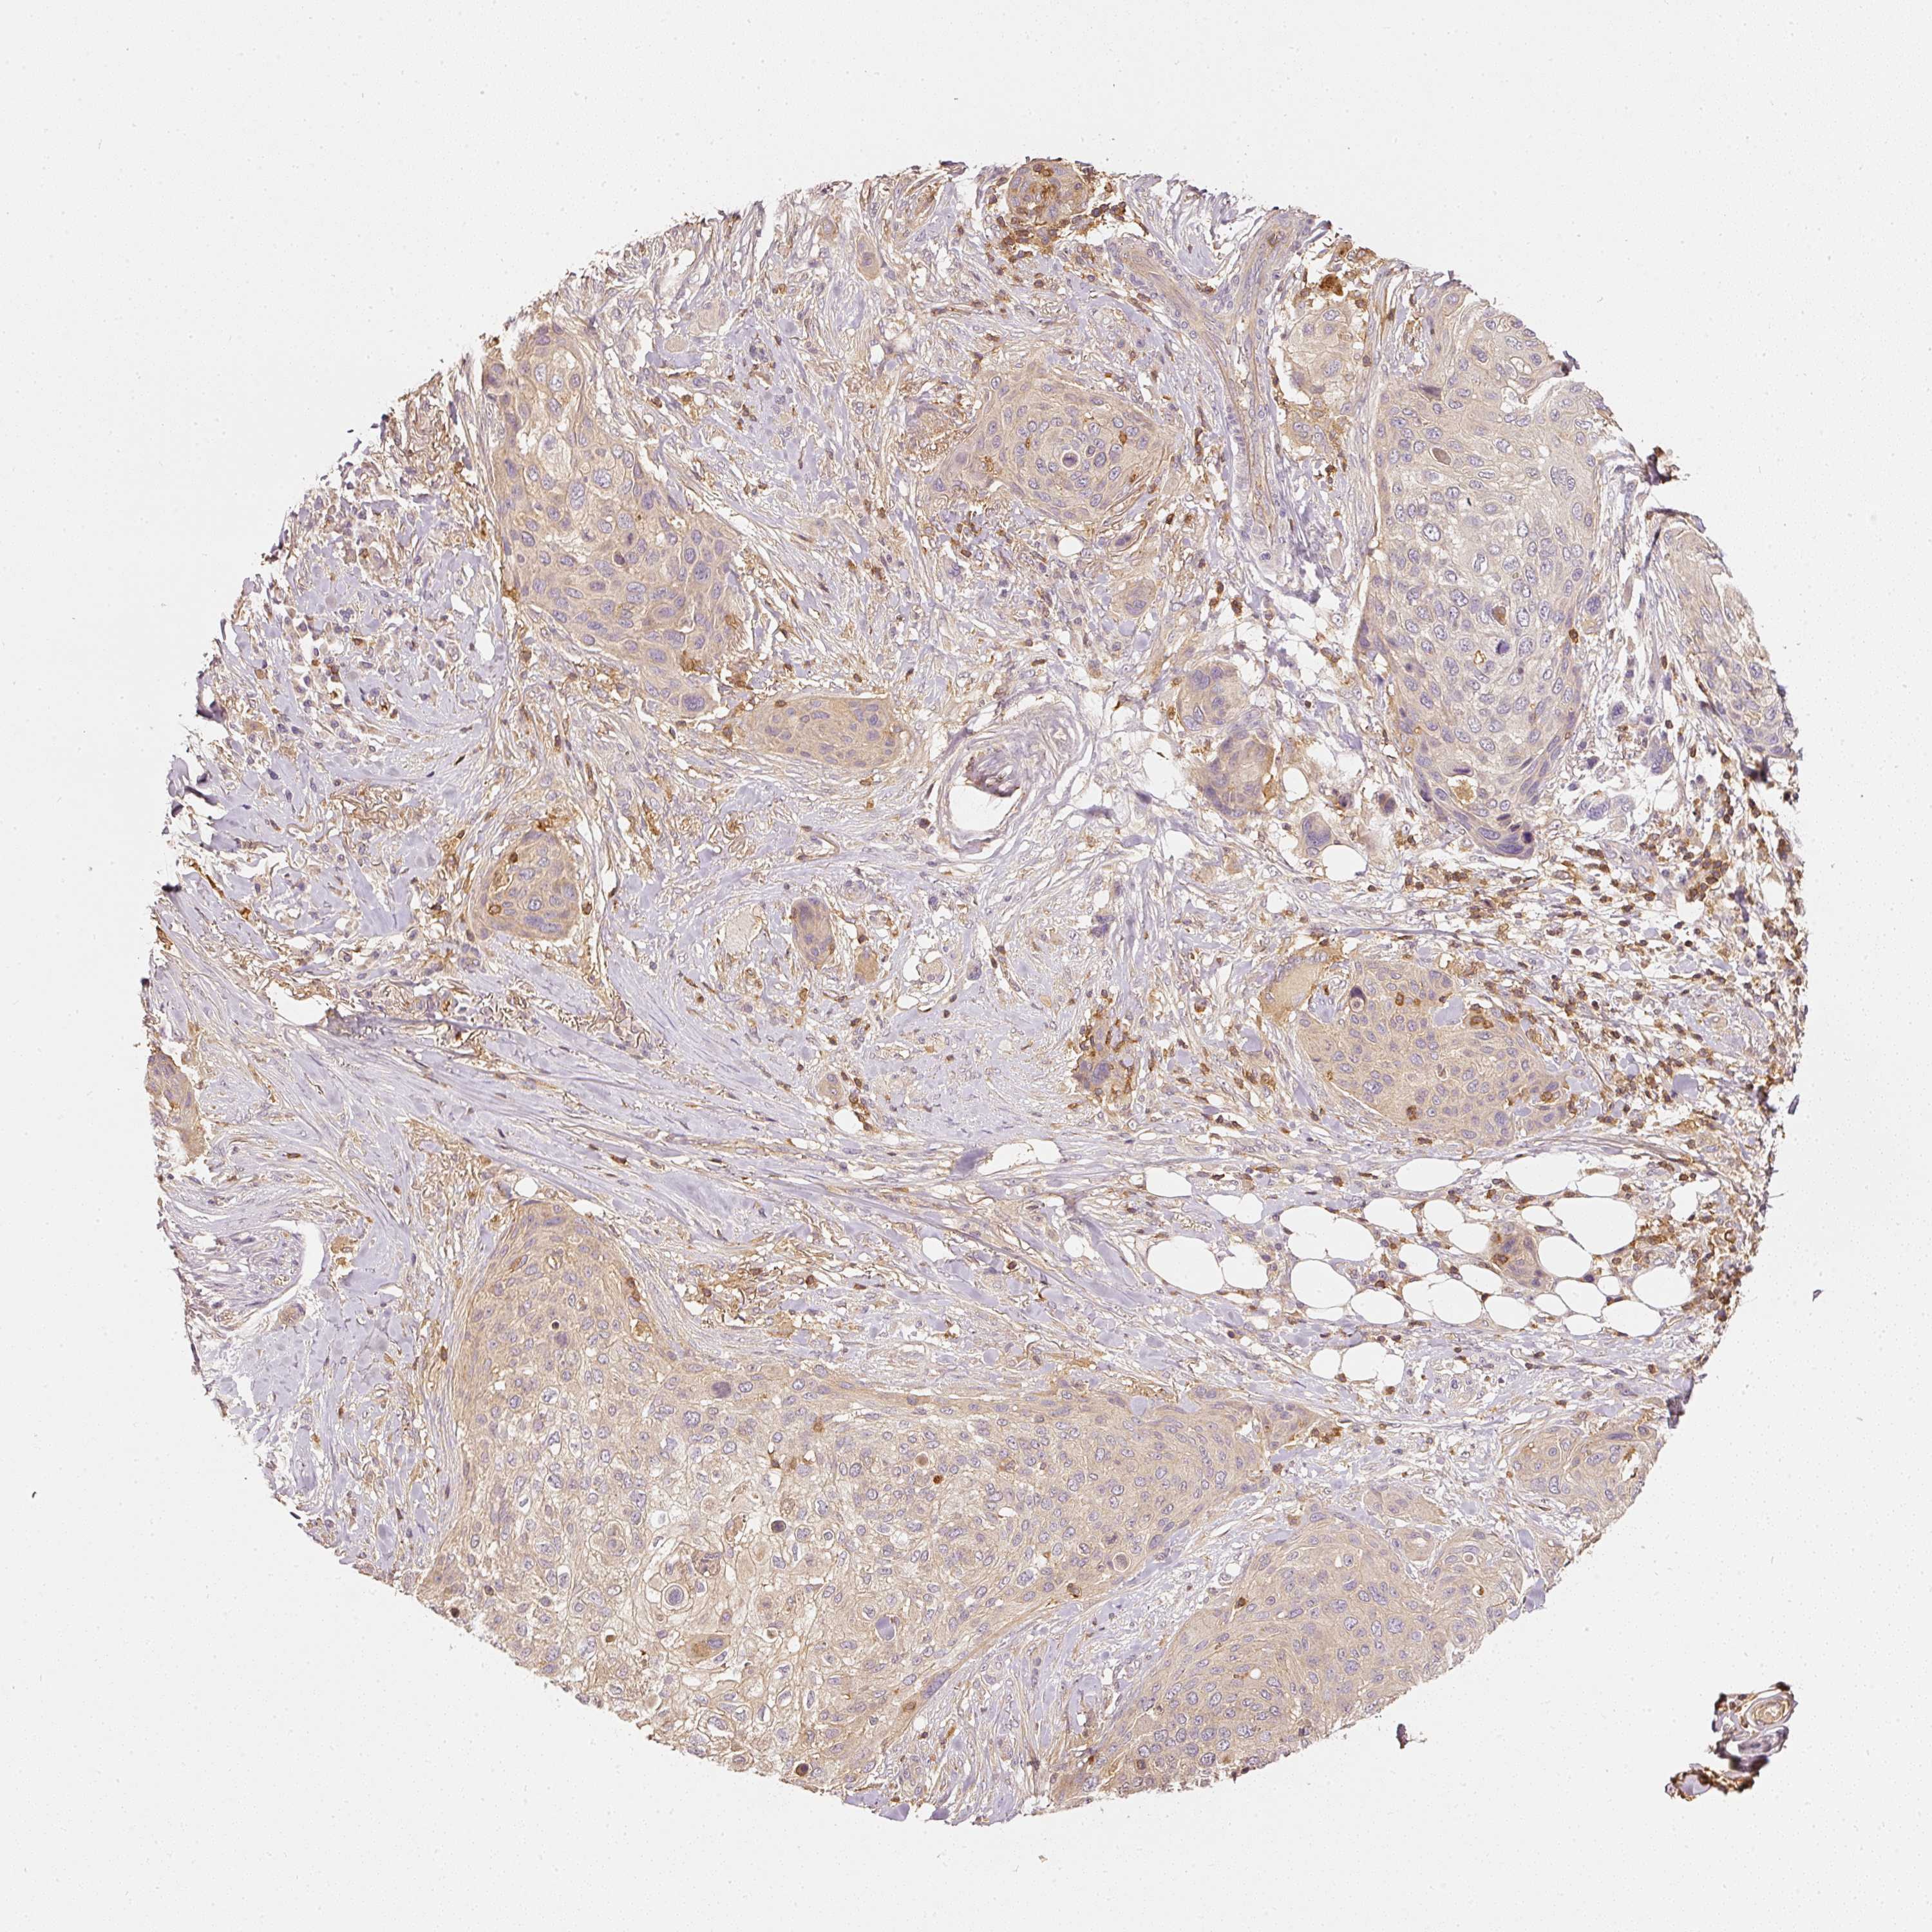

SKIN CANCER - Protein expressioni

A mouse-over function shows sample information and annotation data. Click on an image to view it in a full screen mode. Samples can be filtered based on level of antibody staining by selecting one or several of the following categories: high, medium, low and not detected. The assay and annotation is described here.

Each image is clickable and will lead to virtual microscopy that enables deeper exploration of all samples and also displays staining intensity scores, fraction scores and subcellular localization as well as patient and tissue information for each sample.

Antibody CAB033987

Squamous cell carcinoma, metastatic, NOS